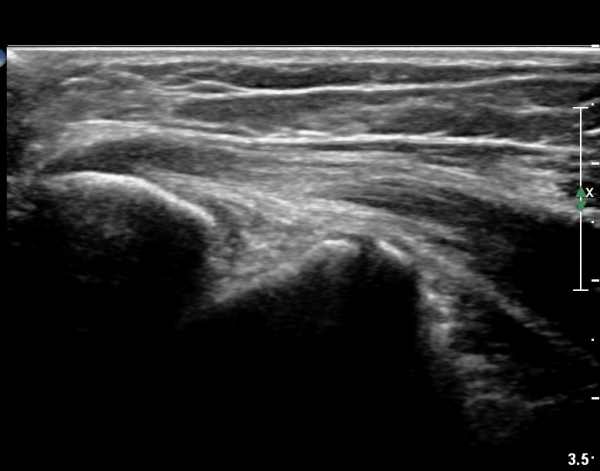

ŽÃËÀÚ¸¦ Á¶±Ý À̵¿ÇÏ´Ï °Ç ÀϺδ Á¤»óÀûÀÎ ¼Ò°ßÀ» º¸À̰í ÀÖ´Ù(±×¸² 3).

°í¿¡ÄÚ Å½ÃËÀÚ(ÇÏŰ½ºÆ½)·Î °üÂû ½Ã °Ç ºÎÂøºÎ°¡ °í¿¡ÄÚ ¼¶À¯ ¾ç»óÀ¸·Î Á¤»óÀûÀÎ ¼Ò°ßÀ» º¸ÀδÙ(±×¸² 4).